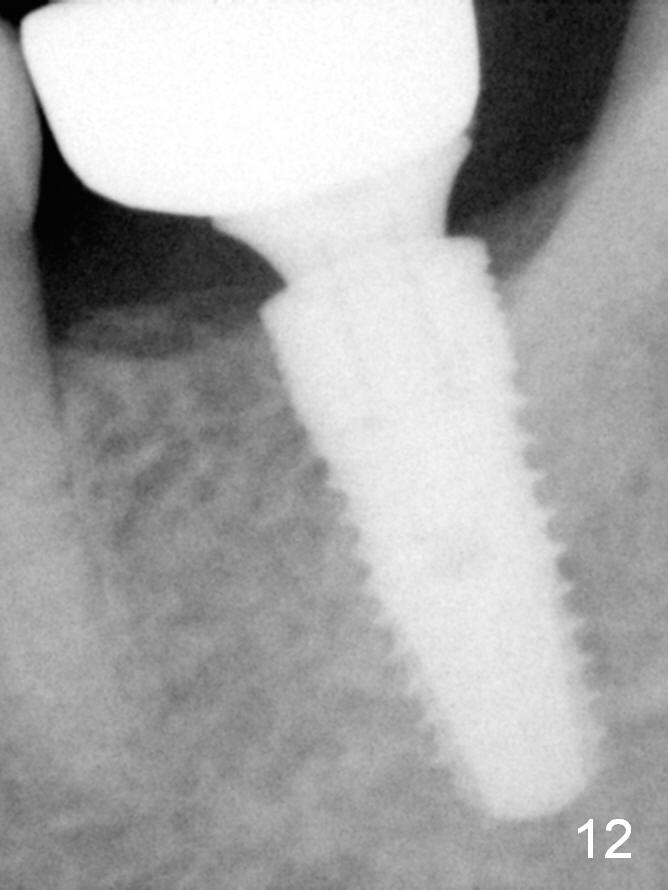

A 48-year-old lady is a dental phobic, requesting extraction of the lower left 2nd molar (Fig.1). She returns for implant placement 9 months post extraction (Fig.2). The ridge is mildly to moderately atrophic. It appears that a 5x12 mm implant is appropriate for the site (Fig.3). For safety, osteotomy is initiated at the depth of 10 mm; it appears that there is enough height for a 12 mm implant (Fig.4). The depth is controlled by drill stopper (Fig.5 S). Finally a 5x12 mm implant is apparently safely placed (Fig.6). A healing abutment is placed and the incision is sutured with 4-0 Chromic gut (Fig.7). Perio dressing is applied around the healing abutment for wound protection (Fig.8). It appears that the healing abutment (Fig.8': *) helps stabilize the perio dressing, which remains in place 1 week postop. When the perio dressing is removed, the wound around the healing abutment is healing (Fig.9). There is no bone loss around the implant 3 months postop (Fig.10 (H: healing abutment), or 16 months postop (i.e., 9 months post cementation, Fig.11,12). The patient complains of pain when she chews with the implant crown, but pain stops whenever she does not bite. Percussion does not elicit any discomfort. The gingiva is healthy. There is possibility of the buccal plate being thin or the lingual plate being perforated in the submandibular fossa. If the discomfort remains the same next 6 months, CBCT will be prescribed.